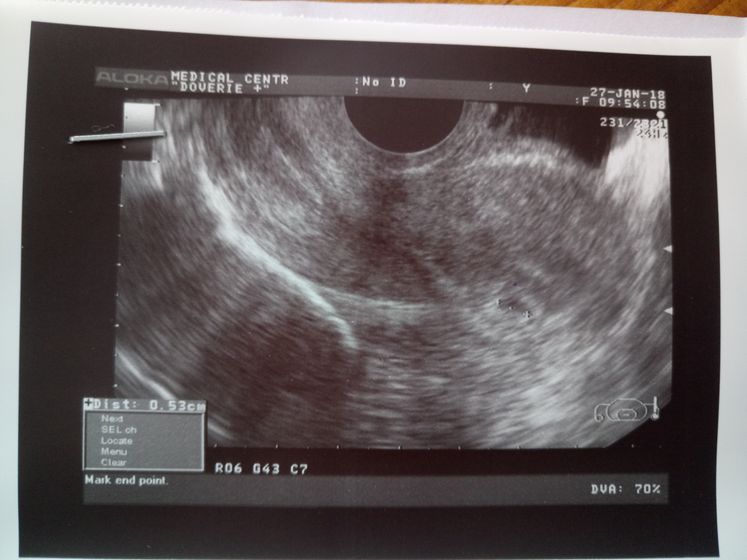

Сходила к врачу, сделала мне узи, поставила 5 недель. Сказала начать пить фолиевую кислоту и дюфастон. Может это из-за выкидыша в 17 лет? Перестраховка?